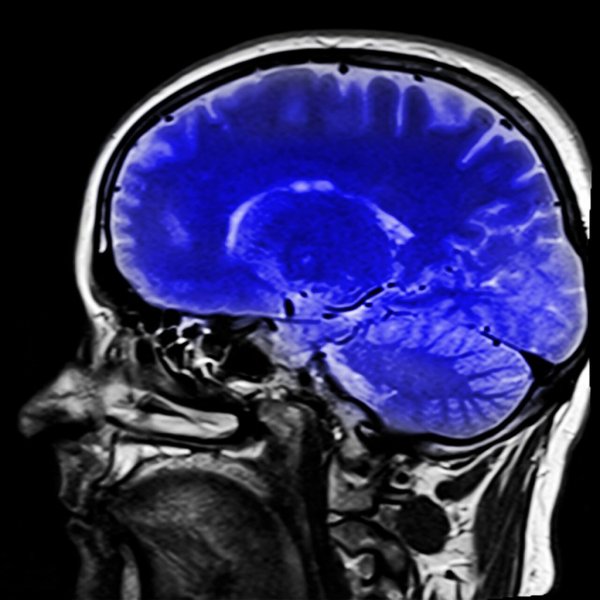

그리하여 의사들이 이 증후군을 진단하는 것을 돕는 신경학적 테스트가 있다. MRI는 어떤 종류의 뇌졸중이 발생했는지 보여줄 수 있고, 무엇인지 알아내는 데 도움을 줄 것이다.

양전자 방출 단층 촬영술(PET)과 전두엽 촬영술(EG)은 의사들에게 환자의 뇌 활동에 대한 정보를 제공한다. PET 스캔은 뇌 신진대사가 정상인지 확인할 수 있게 해준다. 결과가 정상으로 나온다면, 락트인 신드롬처럼 여전히 모든 뇌 기능을 가지고 의식하고 있다는 것을 의미한다.